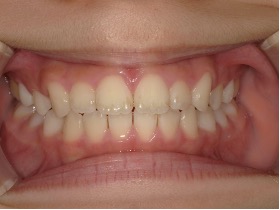

| 年齢・性別 | 8歳11ヶ月の男児 |

|---|---|

| 主訴 | 上顎の永久歯の位置がおかしいとのことで来院。萌出していない右上の前歯の状態に不安を抱えられていました。 |

| 治療期間・回数 | 約3年2ヶ月 |

| 費用 | 440,000円(税別) |